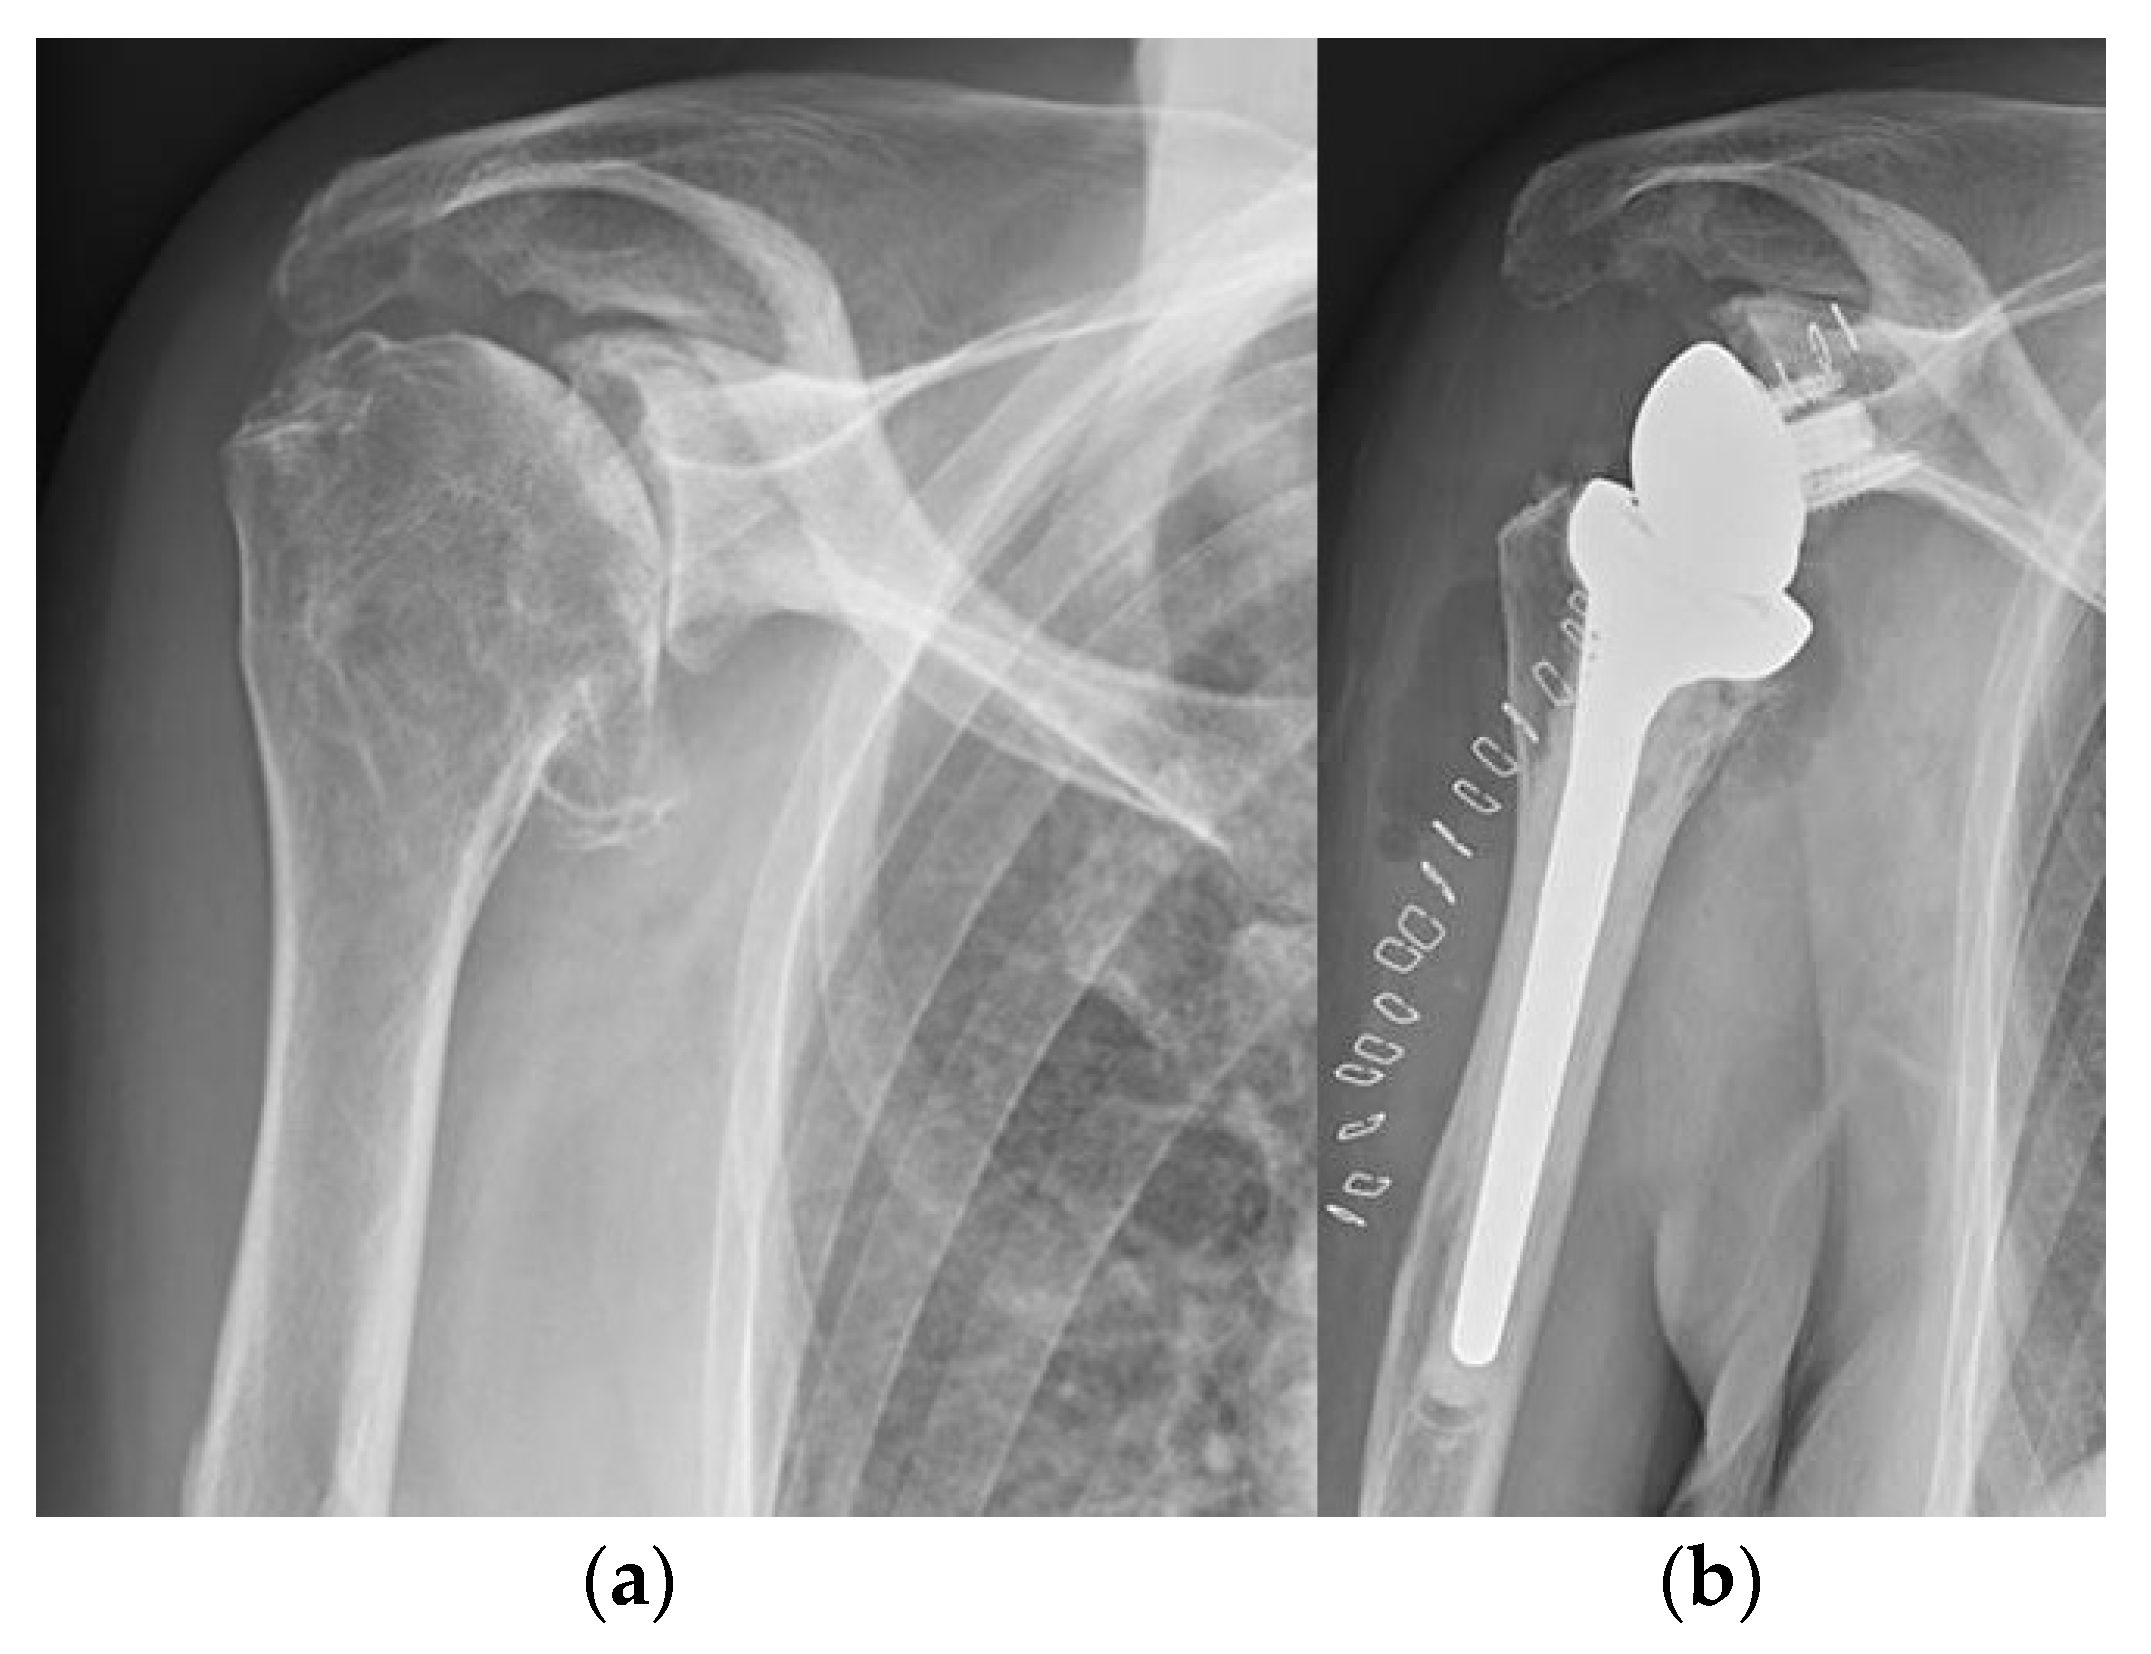

5.2. Shoulder

- Mattei, L.; Mortera, S.; Arrigoni, C.; Castoldi, F. Anatomic Shoulder Arthroplasty: An Update on Indications, Technique, Results and Complication Rates. Joints 2015, 3, 72–77. [Google Scholar] [CrossRef]

- van den Bekerom, M.P.J.; Geervliet, P.C.; Somford, M.P.; van den Borne, M.P.J.; Boer, R. Total Shoulder Arthroplasty versus Hemiarthroplasty for Glenohumeral Arthritis: A Systematic Review of the Literature at Long-Term Follow-Up. Int. J. Shoulder Surg. 2013, 7, 110–115. [Google Scholar] [CrossRef] [PubMed]

- Trofa, D.; Rajaee, S.S.; Smith, E.L. Nationwide Trends in Total Shoulder Arthroplasty and Hemiarthroplasty for Osteoarthritis. Am. J. Orthop. 2014, 43, 166–172. [Google Scholar] [PubMed]

- Zhang, B.; Chen, G.; Fan, T.; Chen, Z. Resurfacing Hemiarthroplasty versus Stemmed Hemiarthroplasty for Glenohumeral Osteoarthritis: A Meta-Analysis. Arthroplasty 2020, 2, 25. [Google Scholar] [CrossRef] [PubMed]

- Chawla, H.; Gamradt, S. Reverse Total Shoulder Arthroplasty: Technique, Decision-Making and Exposure Tips. Curr. Rev. Musculoskelet. Med. 2020, 13, 180–185. [Google Scholar] [CrossRef]